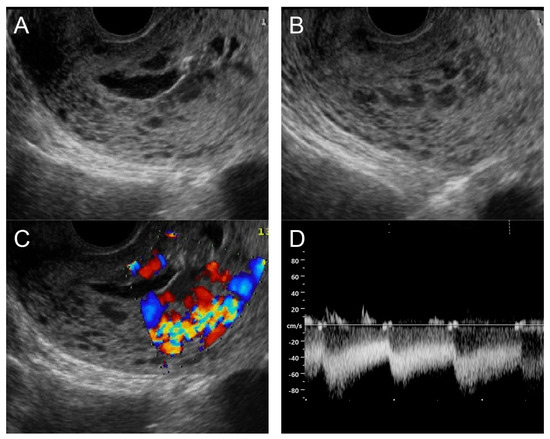

(A) Transvaginal ultrasound: sagittal scan of the uterus showed several dense small anechoic/hypoechoic tubular structures, mainly running to the endometrium, scattered throughout the anterior wall of the uterus; a thin endometrium; no other specific lesions of the uterus. There was anechoic fluid collection in the uterine cavity. (B) Cross-sectional scan of the fundus showed lesions with poorly defined outlines, containing several dense small anechoic/hypoechoic tubular structures, packed in the anterior wall. (C) Color flow mapping showed hyper-vascular areas in the myometrium, without well-defined lesion borders; multidirectional flow mainly localized at the anterior wall and the fundus. The main differential diagnosis was adenomyosis or gestational trophoblastic disease. (D) Spectral Doppler showed a high peak systolic velocity (~50 cm/s) with a low resistance index of 0.3. Note that in differentiating from adenomyosis, which sometime shows multiple minute anechoic or spongy-like areas but not lacunar lakes or tortuous vessels, adenomyosis is characterized by the absence of flow or minimal flow or by the presence of straight, scattered vessels traversing a hypertrophic myometrium [18,19], typically not containing a high flow peak systolic velocity, as seen in AMV, as mentioned earlier.